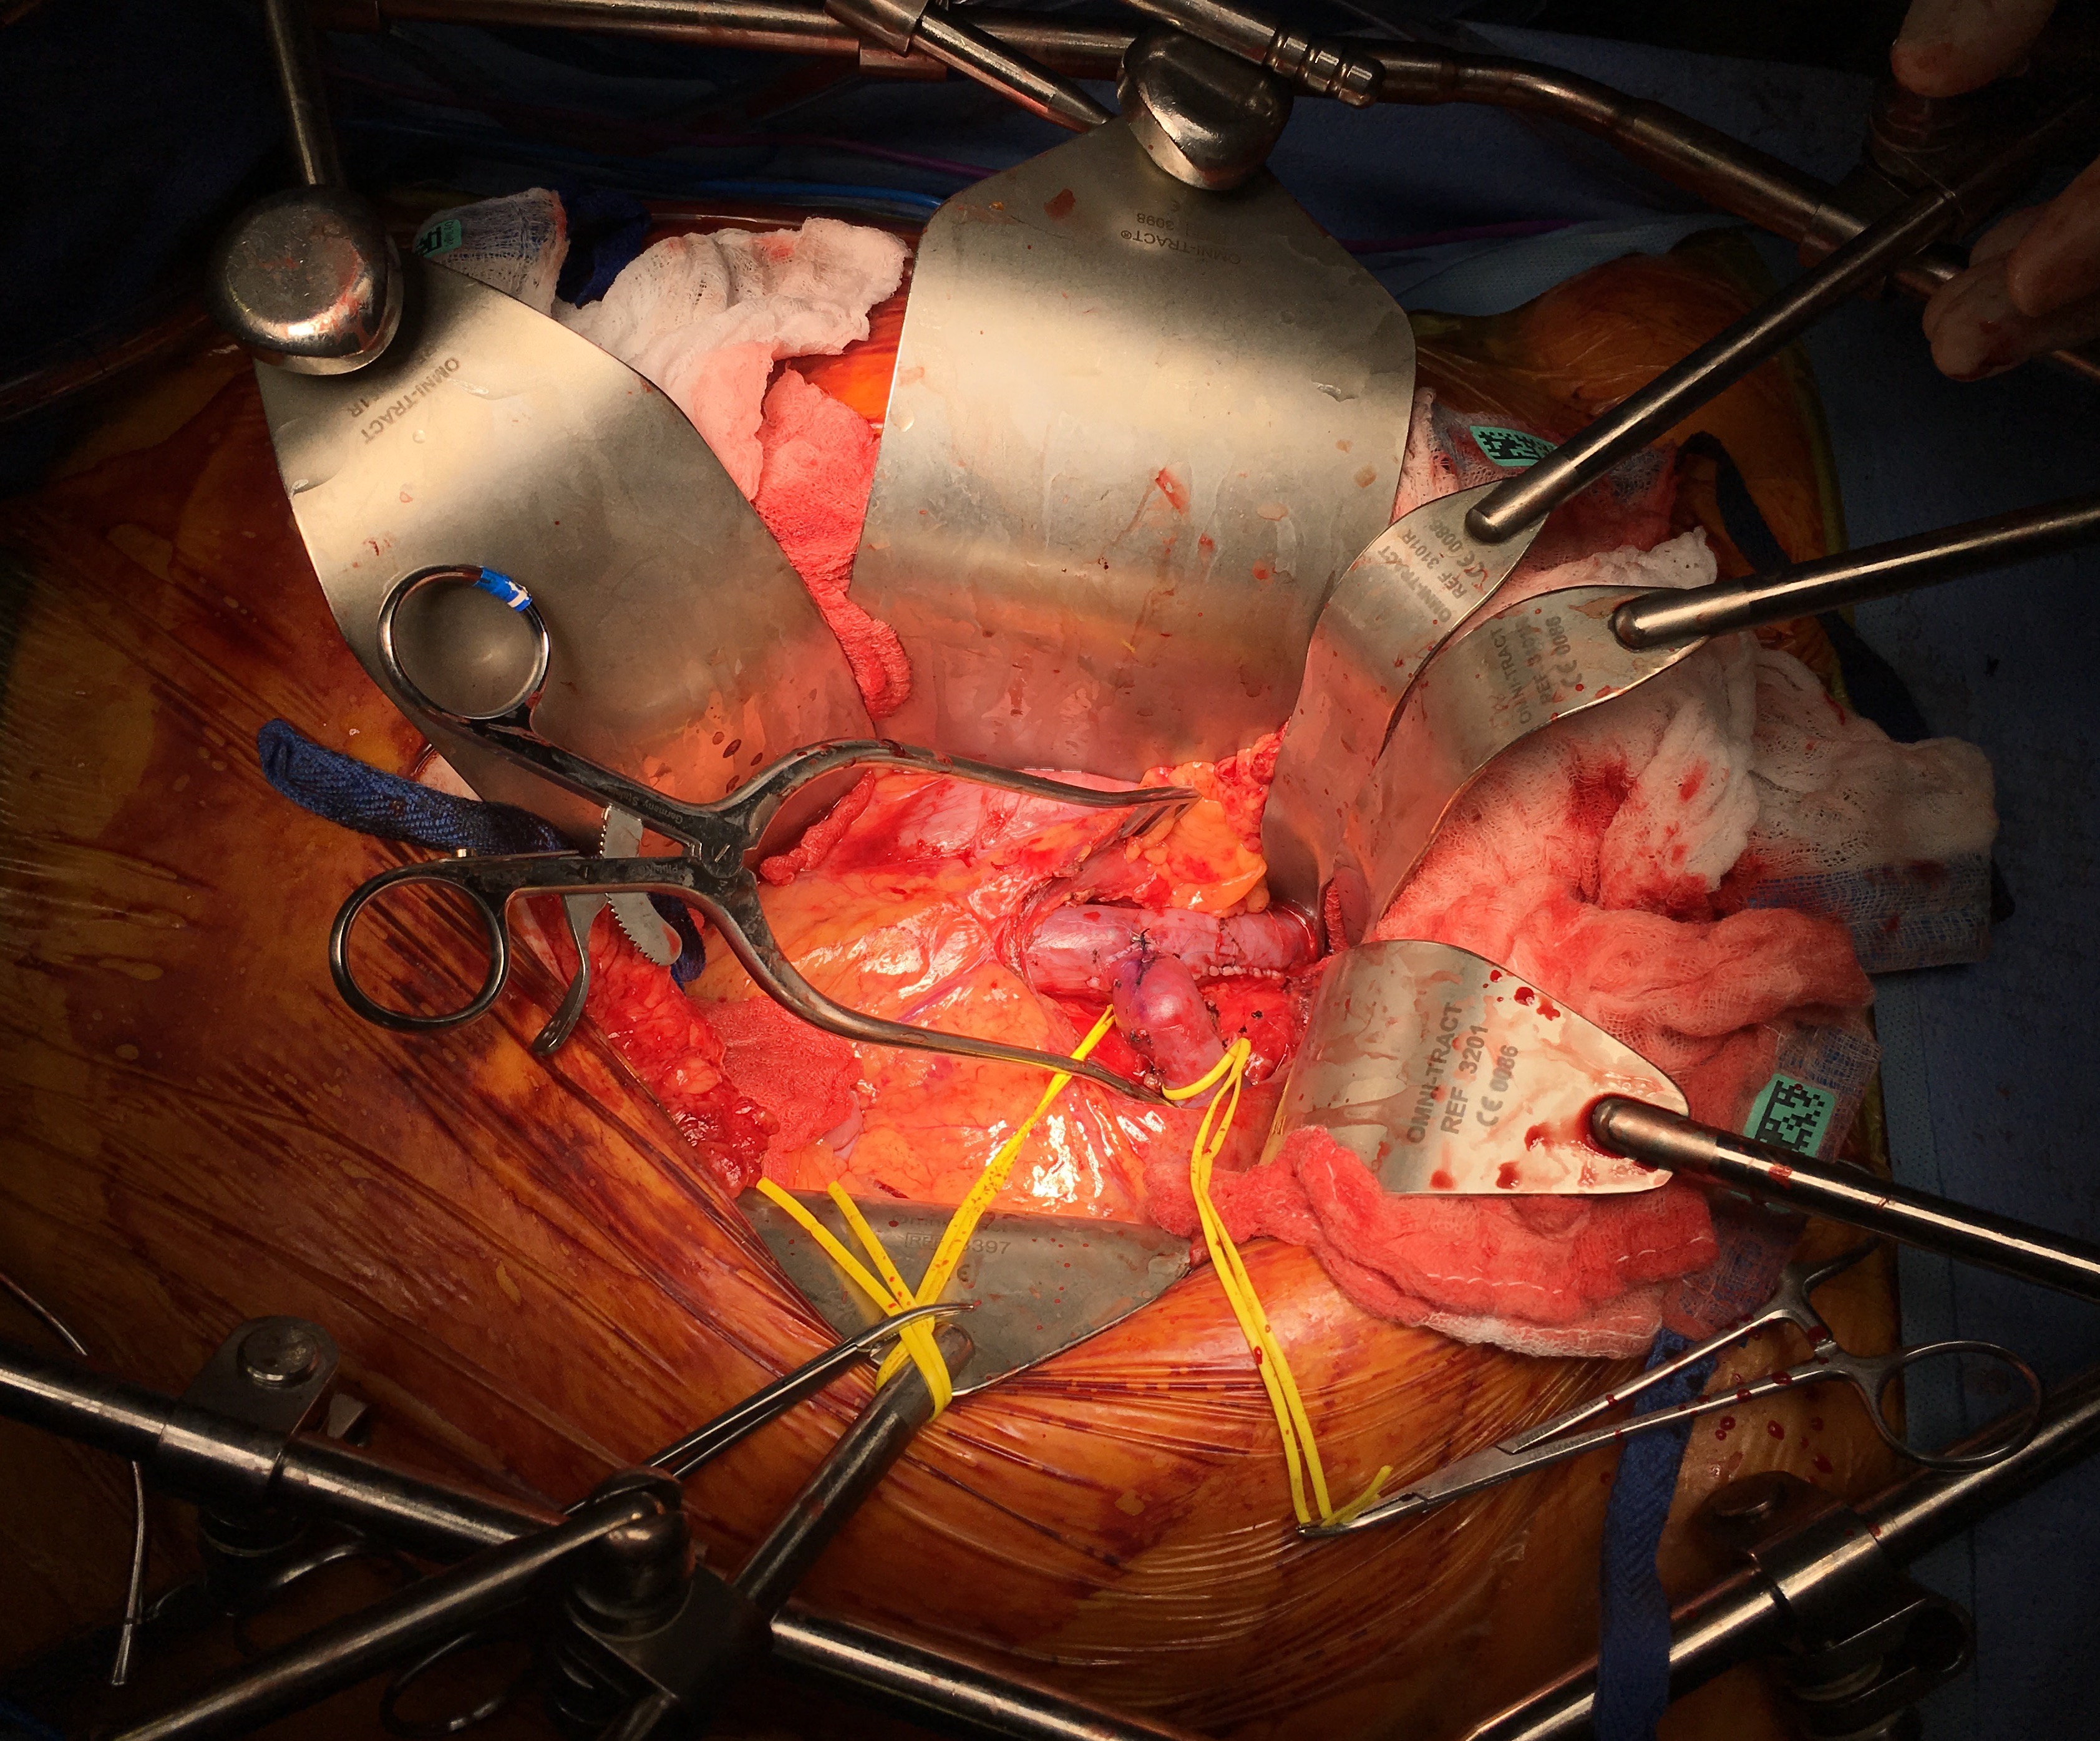

He was prepared for surgery with echocardiography (normal) and lab testing (normal LFT’s, CBC, BMP, INR), and taken to the OR. A chevron incision was made to broadly expose the area. The median arcuate ligament was exposed and released -there was dense tissues proximal to the dilated celiac axis. The aneurysm was dissected out and the small branches were carefully dissected out and controlled. It is easy to injure the branch hepatic arteries which can constrict on dissection.

A suitable length of saphenous vein was harvested and prepared. The three vessels diagrammed above did not present themselves suitable for a single Carrel patch so I sewed end to end to a patch incorporating the right hepatic and gastroduodenal arteries, and performed a sequential side to end anastomosis to the left gastric artery.

IMG_0926.jpg

After heparinizing and clamping, the renal tributary was taken with a 5mm cuff –this would ensure proper length without narrowing the IVC.

The vein was anastomosed and flow was excellent by pulse Doppler.

IMG_0927.jpg